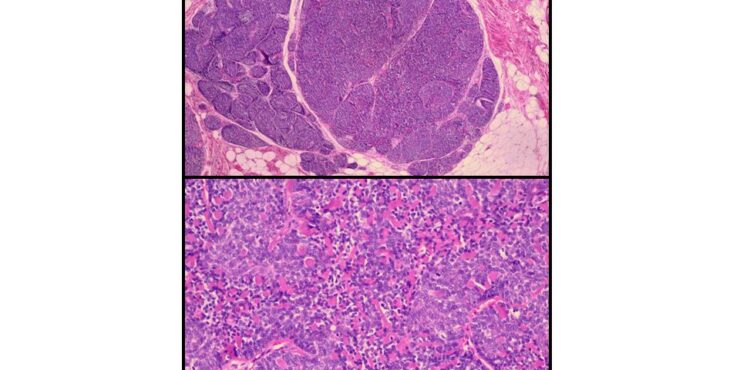

Read MoreSpitz naevus (juvenile melanoma) = وحمة سبيتز _الميلانوم الفتوي